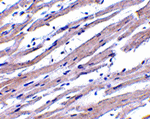

Immunohistochemistry of Apaf1 in human heart tissue with Apaf1 antibody at 1 ug/mL.